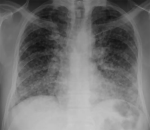

由于受传统观念影响,一些人认为肺结核是不治之症,特别是在农村地区,患肺结核便背上...

及时发现结核病人,积极治疗结核病人。这是最有效的预防措施之一。我们知道结核病人,...

学校是师生高度集中、接触频繁密集的场所,一旦发生结核病,不仅影响师生身体健康,而...

结核病是传染病,危害健康负担重,健康教育不放松,核心知识须牢记,防病意识要提升 ...

小儿肺结核多为原发性肺结核,是由于结核杆菌第一次侵入肌体而致病的,90%以上的原...

全国第四次结核病流行病学抽样结果显示,老年结核病患病率高于其他各年龄组患病率。老...

肺结核患者咳嗽、打喷嚏或大声说话时,喷出的呼吸道飞沫中会含有大量的结核菌,健康人...